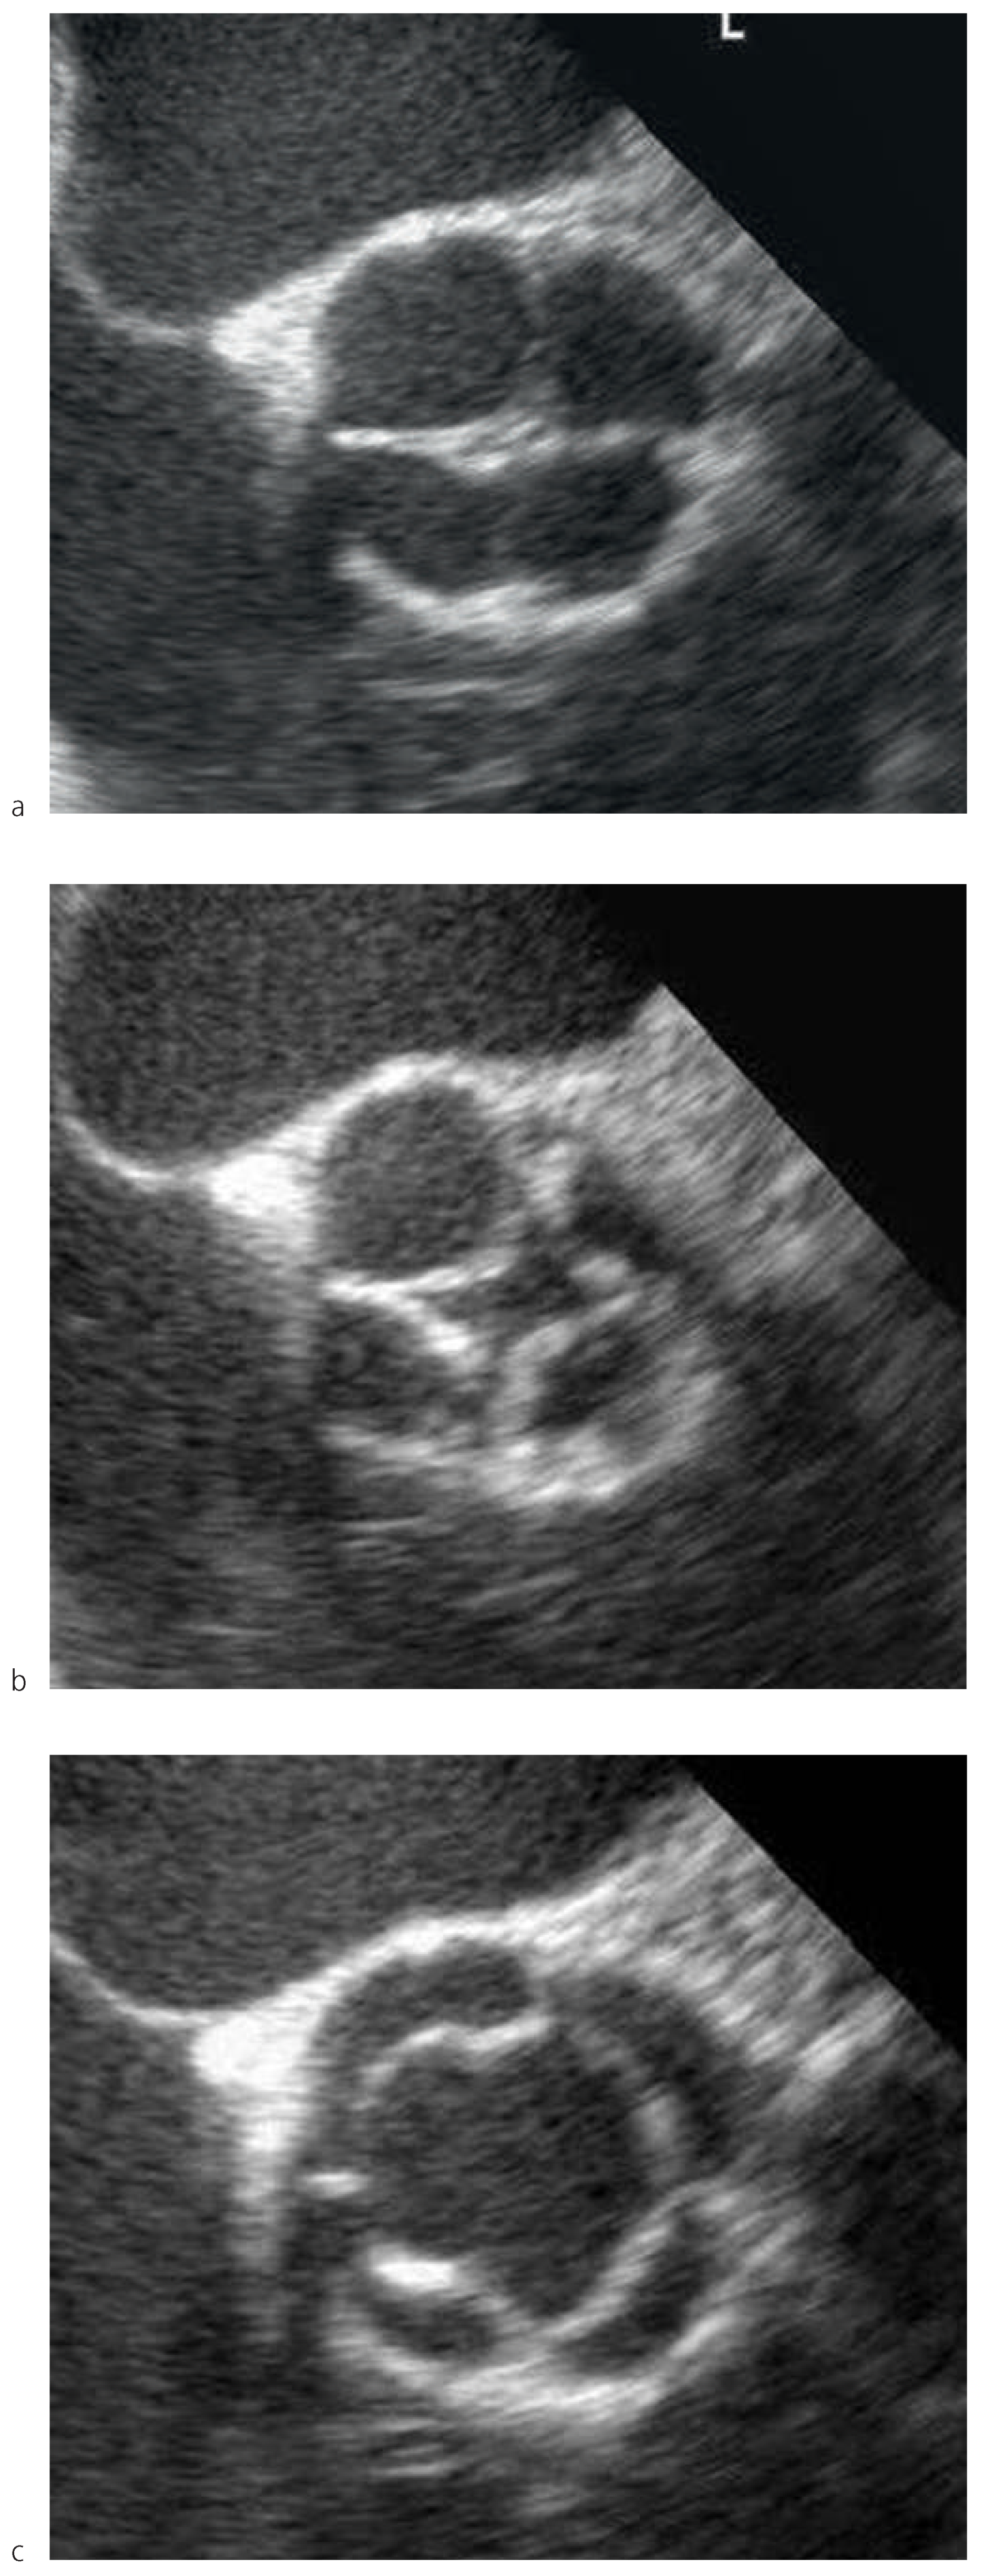

Dieser Befund bestätigte sich in der transösophagealen Echokardiographie (Figure 2a–c and Figure 3). Es fanden sich vier Kommissuren, welche periphere Fusionen der Taschen mit kurzen Raphen aufwiesen.

Die vier Taschen der QAK unserer Patientin waren symmetrisch konfiguriert, wenig verdickt und gut beweglich. Im Farbdoppler zeigte sich eine leichte zentrale Aorteninsuffizienz am Koaptationspunkt der vier Taschen. Der Hauptstamm der linken Koronararterie zeigte einen orthotopen Abgang. Nebenbefundlich fand sich ein PFO.

Figure 2. Transösophageale Echokardiographie: QAK in verschiedenen Phasen des Herzzyklus. Die geschlossene Klappe erinnert an ein Kreuz.

Figure 3. Transösophageale Echokardiographie, Längsschnitt.